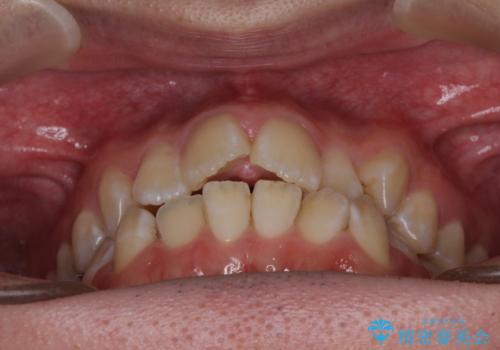

- 上下前歯のデコボコを気にして来院された患者様です。

ワイヤー矯正でもマウスピース矯正でも可能でしたが、短期間で、自身の手を煩わせることなく治療を行いたいとのことで、ワイヤー装置にて矯正治療を行うこととしました。